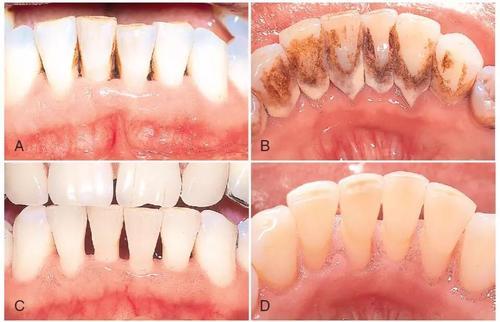

(1)洗牙能够去除牙龈上的牙石、菌斑和牙面上沉积的色素,还可以抛光牙面,以减少菌斑和牙石的沉积,同时洗牙还可以有效减轻牙龈炎、牙周炎,有利于口腔健康。

(1)洗牙如果操作不当,如加压或在牙面上停留时间过久,会在牙面上留下细小划痕,通常情况下这种划痕可通过抛光来弥补。

(2)洗牙会将牙齿缝隙中的牙垢清除,从而导致牙齿缝隙变大,如果牙齿患有牙周病的话,不及时治疗会使牙齿发生松动现象。

即使是洗牙这种最基本的操作,也需要找比较专业的口腔门诊或者医院,不当的操作有可能导致牙隐裂,而且洗牙后的抛光是必须的,抛光是将洁牙机在牙表面留下的划痕去掉,因为粗糙的平面比光滑的平面更容易堆积细菌。